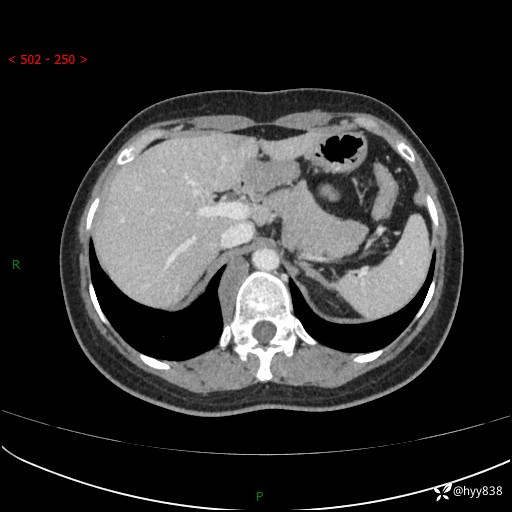

现在都流行跨界,病变也不例外,从腹膜后长到胸腔了---结果公布~

主诉:体检发现右侧腹膜后肿物1天

简要病史:患者于1天前因体检发现右旁肾占位,无肉眼血尿,无畏寒发热,无咳嗽咳痰,无腰腹部疼痛不适,无尿频尿急症状,起病来,患者未行特殊治疗,为求进一步诊治,门诊以"右侧腹膜后肿物"收治入院。 发病来患者精神、饮食、睡眠良好,小便如上,大便正常,体重无明显变化。

临床诊断:腹膜后肿物

上腹部CT增强(动脉期+实质期)(外院平扫)